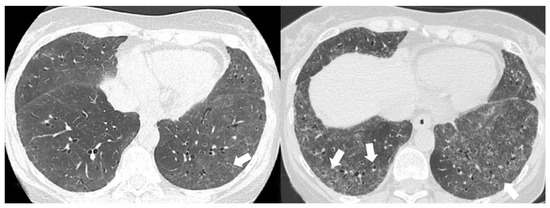

- Chronic progressive fibrosing ILD (reticulation and honeycombing with minimal GGOs on HRCT scans, related to fibrotic NSIP or UIP) [43];

| Lesions | GGO, reticulations, consolidations | consolidations, GGOs | |

| Distribution | Homogeneous; lower lung lobes, along bronchovascular bundles and lung periphery; loss of volume of lower lobes | Patchy; peripheral lower lobes or along the bronchovascular bundles | |

| CT pattern | NSIP OP NSIP-OP UIP DAD-unclassifiable | 50% 20% 25% 10% +/− | 20% 50% 25% <5% ++ |